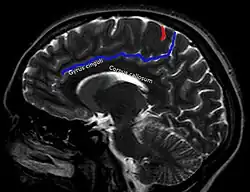

In der Computertomographie und Magnetresonanztomographie ist für die korrekte Lokalisation eines Befundes eine sichere Identifikation des Sulcus centralis oft einer der ersten Schritte. Hierfür haben sich in Abhängigkeit von der Schnittebene verschiedene Strategien etabliert.[4] Beispiele:

| Axial | Sagittal |